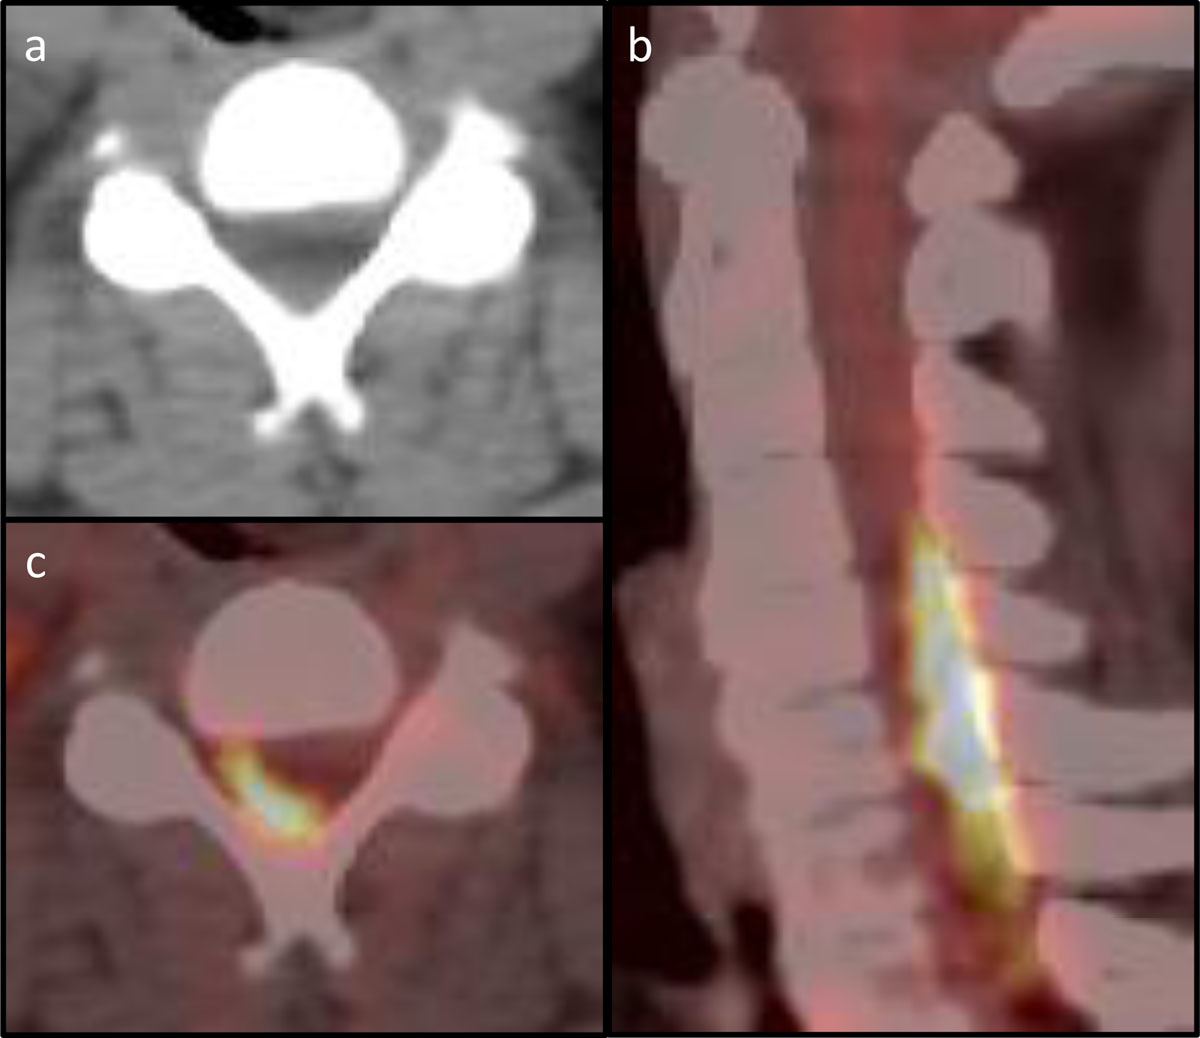

Figure 2

PET-CT of the cervical spine. (a) Axial CT at vertebral level C4 with barely visible posterior epidural mass. (b) Axial PET-CT of vertebral level C4 with notable FDG-avid disease in the spinal canal. (c) Sagittal PET-CT with FDG-avid disease posteriorly within the spinal canal.

In retrospect, the FDG-PET-CT scan already showed FDG-avid disease in the cervical spinal canal consistent with intraspinal extradural lymphoma, which was inconspicuous on the cross-sectional anatomical information provided by the CT part of the examination (Figure 2).

Last, despite avid FDG-uptake, involvement of the spinal canal was overlooked on PET-CT performed days before the onset of paraplegia.